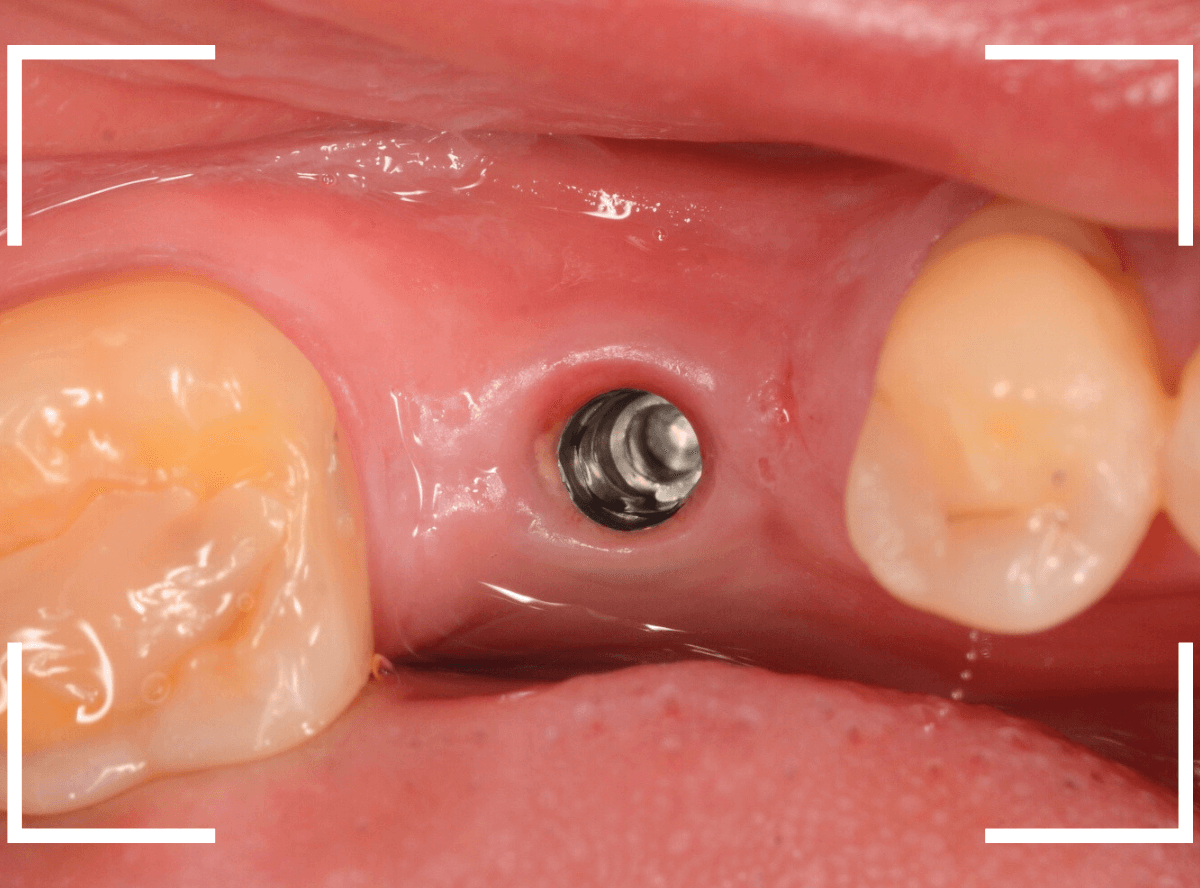

手術当日、インプラント体を埋入した直後です。

この状態で、しばらく経過観察をします。

インプラント体の周囲の骨と歯肉が落ち着くのを待って、型取りをします。